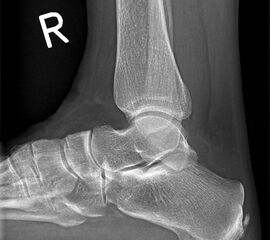

Fersenbein lateral

Positionierung:

• Patient in Seitenlage.

• Fuß mit der Außenseite aufliegend.

• Ferse liegt parallel zum Tisch.

• Röntgenröhre 90° zur Senkrechten.

• Zentralstrahl von lateral nach medial, zentriert auf das Fersenbein ca. 1-2 Querfinger distal der Malleolen.

Kennzeichen des Röntgenbildes:

• Seitliche Darstellung des Fersenbeins mit scharfen Knochenkonturen.

• Gut einsehbares unteres Sprunggelenk (Articulatio talocalcaneonaviculare).

• Gut einsehbares Gelenk zwischen Calcaneus und Os cuboideum.

Besondere Bemerkungen zum Beispielbild:

• Darstellung der Kalkaneus seitlich.

• Kleiner Traktionssporn im Insertionsbereich der Achillessehne.

• Großes Os trigonum dorsal des Talus.